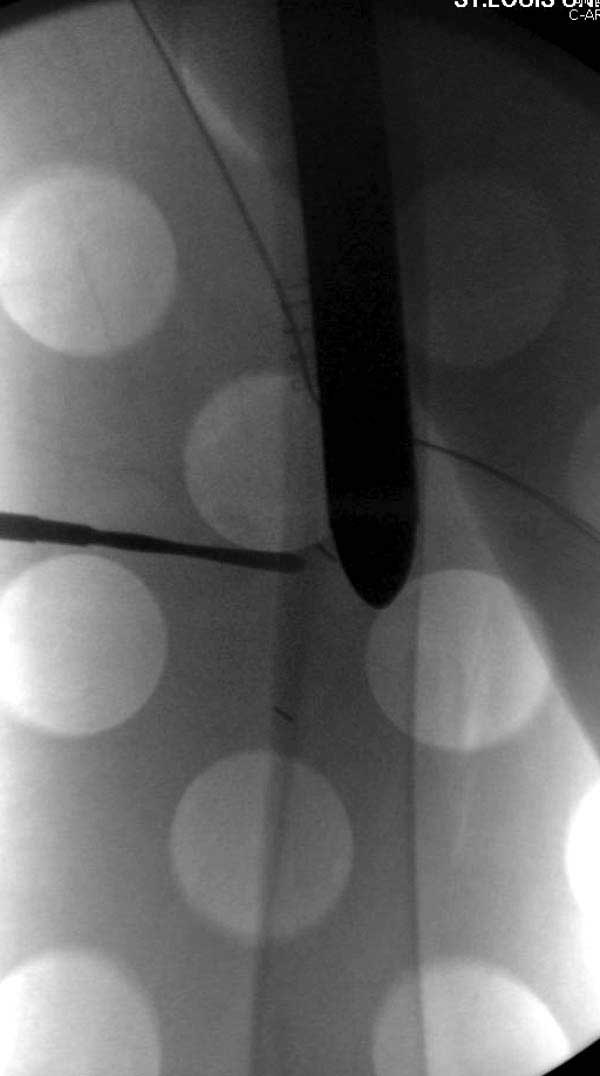

Сеньоры-пэры ревизировали гвоздем, шуруп поставили по той же дорожке, только поглубже. Да еще и bone graft не пожалели. "Результат" уже был через 2 дня.

Первые снимки показывают технические погрешности установки DHS. Не была достигнута репозиция, конечность в флексии и шейка в ротации. Сегодня все меньше обращают внимание на параметры для оценки репозиции (S контуры Lowell в обеих проекциях и Garden Alignment Index, в норме 155 и 180 градусов), хотя такие простые тесты помогли бы дорепонировать смещение. Винт находится сзади в головке, что при нагрузке поменяет вектор и вместо компрессии в линии перелома срежет головку-Cut Out!

Вторая операция- это фаза сохранения головки бедра. Желательно приложить все усилия и сохранить головку, но, как видно, “фиаско” продолжается. Здесь вместо нейтрализации сил между медиальной и латеральными сторонами была попытка удержать варус. Варус не удержать ни деротационными шурупами о котором говорили и не костными стружками вбитые в шейку, потому что вся нагрузка упирается в головку.

Как отметил Евгений, 95 degree Blade Plate Fixed Angle device расчитана на восстановление взаимоотношении между головкой и диафизом, а все остальные фиксаторы (Gamma, Afifuxus и др.) работают за счет нагрузки в верхнем полюсе головки. Верхний полюс успели разрушить, и в головке единственное место, который смог бы удержать широкий клинок конструкции, это медиально-низкий сегмент. После установки клинка засчет дистракции можно удлинить конечность на 15мм, а добавленный в дефект ауто-графт закончил бы дело.

Третья операция-продолжения усилии “синьорами пэрами” по разрушению нормальной анатомии. Крест на головку! По видимому возраст позволяет биполярную конструкции, и при дефекте calcar пошли на обычный цементный. Ягодичные мышцы потеряли связь с вертелом, т.е. отсутствует верхний удержатель, и результат “a Big Screw Up!” Снимки вызывают головокружение!